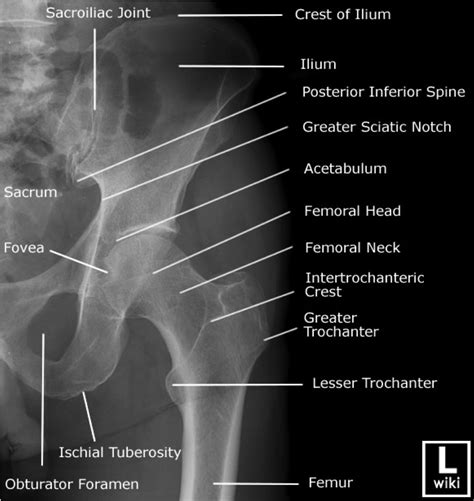

Interpreting a Normal Hip X Ray requires a trained eye. Radiologists look for specific features to determine the health of the hip joint. Key elements include:

• Bone Density: The density and structure of the bones should appear uniform and without any fractures or lesions.

• Joint Space: The space between the femoral head and the acetabulum should be consistent and without narrowing, which could indicate arthritis.

• Alignment: The femoral head should be properly seated within the acetabulum, and the neck of the femur should align correctly with the shaft.

• Soft Tissues: The surrounding soft tissues should appear normal, without any swelling or abnormalities.